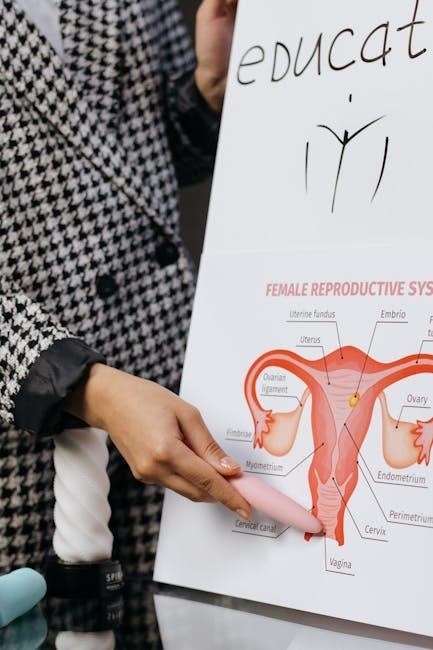

The superior thoracic cavity contains the heart and lungs, while the inferior abdominopelvic cavity houses the abdominal organs (stomach, intestines, liver) and pelvic organs (bladder, reproductive organs).

A good study guide will detail the membranes lining these cavities (serous membranes) and the organs within. Diagrams illustrating the location of each cavity and its contents are essential for visualization. Understanding these spatial relationships is fundamental to grasping physiological processes and clinical applications.